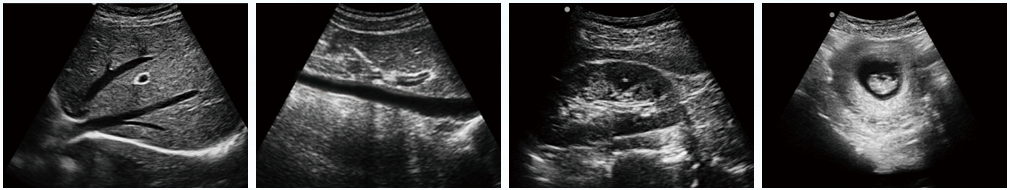

設備用途說明:主要應用于腹部、淺表組織、生殖系統、泌尿系統等器官的檢查

全數字成像技術,真實、細膩地顯示組織結構;